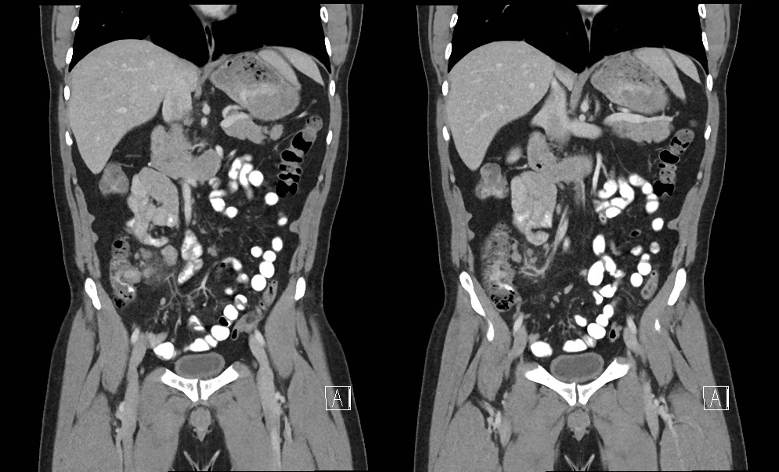

복부 초음파 우선, 연장아에서는 CT 고려 가능

CT 소견: Appendiceal diameter > 7mm (진단적), 충수돌기 비후 및 주변 fat stranding, appendicolith, 충수돌기 내부의 fluid

초음파 소견: tubular wall thickening - Appendiceal diameter > 6mm (진단적), noncompressible (배를 눌렀을 때 충수돌기가 눌리지 않음), 도플러 혈류 증가